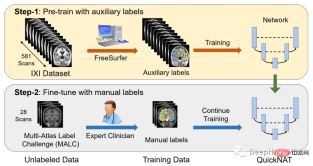

One of the main challenges in scaling CNN models to brain segmentation is the limited availability of human-annotated training data. The authors introduce a new training strategy that utilizes large datasets without manual labels and small datasets with manual labels.

First, use existing software tools (such as FreeSurfer) to obtain automatically generated segmentations from large unlabeled datasets, and then use these tools to pre-train the network. In the second step, the network is fine-tuned using smaller manually annotated data [2].

The IXI dataset consists of 581 unlabeled MRI T1 scans of healthy subjects. The data was collected from 3 different hospitals in London. The main disadvantage of using this dataset is that the labels are not publicly available, so in order to follow the same approach as in the research paper, this article will use FreeSurfer to generate segmentations for these MRI T1 scans.

Although FreeSurfer is a very useful tool for leveraging large amounts of unlabeled data and training networks in a supervised manner, scanning to generate these labels requires up to 5 hours, so here we train the model directly using the OASIS dataset, which is a smaller dataset with publicly available manual annotations.